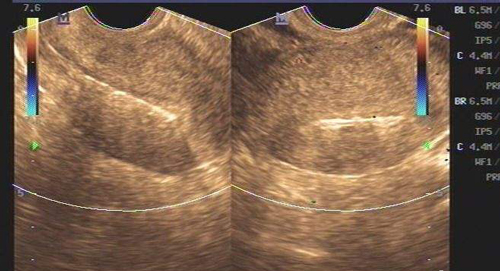

AFC是窦卵泡计数的缩写,是指利用B超彩超等等对卵巢的卵泡数目、大小来进行其的计数手段之一,而窦卵泡常说的是女性卵巢内直径在2-10mm的小卵泡,而通过窦卵泡计数也能够非常好的反应出卵巢储存功能等等。

女性在,最开始进行窦卵泡计数检查的时候,对于什么是窦卵泡计数都会感觉到一定的迷茫,简单的来说窦卵泡就是卵巢中成长出最为原始的3级卵泡,在阴道超声或者彩超的帮助下进行窦卵泡计数,在它们的帮助下,可以最为正确的评估与准确的计数出数量,因为女性的生育能力就是随着时间的改变而改变的,所以在医学上来说,窦卵泡计数是迄今为止最好的办法,能够在任何情况下让人知道卵巢的储存功能,以及在接受试管婴儿手术的时候也要根据这种方法来进行判断卵巢对药物反应,以增加成功率,窦卵泡计数意思就是通过这些办法计算出基础卵泡的个数,从而得到需要的结果。

在2D阴超检查的时候必须进行进行对膀胱排空后方可进行,而常常需要在两个平面进行连续的扫查,找出成像较佳平面,并进行超声调整后再做最为准确的卵泡液与卵巢间质间的对比度。

相对于2D阴超来说3D阴超下过要好一点,3D阴超是同时利用3个垂直平面存储和分析产生体积,通过多平面交叉进行窦卵泡计数检查,将效果发挥到最佳,在较好切面直接进行最佳图像参数和最大采集角,将成像图片质量提升到最高